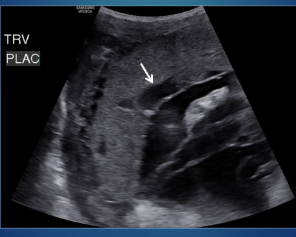

What does the arrow point to?

circumvallate/circummarginate placenta